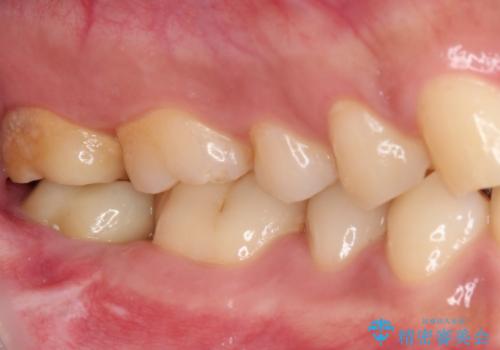

被せものが入れられない 外科処置を行ったセラミック治療

- 奥歯の虫歯治療を希望したものの、歯の高さが足りなくて治療ができないと言われ、来院された患者様です。

レントゲン撮影より、根尖部に病変が認められたため、根管治療を行った後に、歯冠長延長術を行うこととしました。

銀歯の頃は頻繁に外れていたため、不快感が強かったようですが、歯冠長を延長したことで外れにくいクラウンを装着することができ、不快感が改善されました。